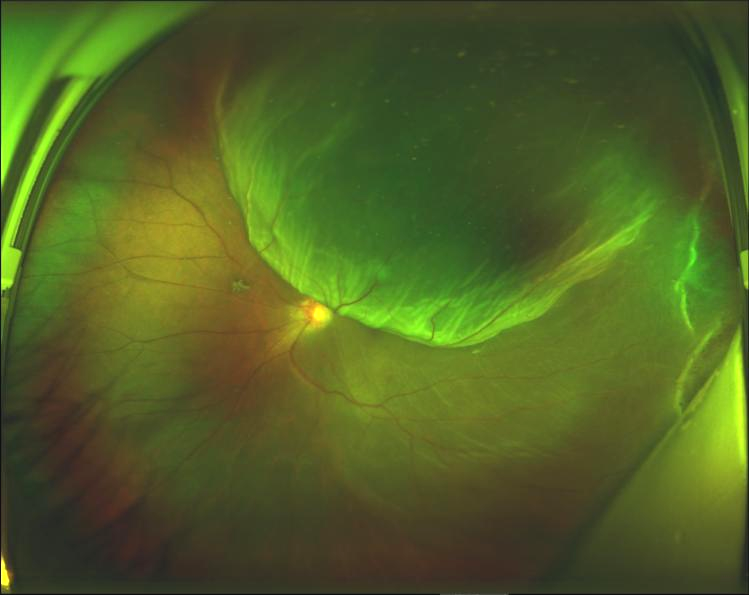

經(jīng)過檢查,陳燕副主任發(fā)現(xiàn)小曾的傷眼已發(fā)生視網(wǎng)膜脫離,需要盡早手術(shù),否則有失明的風(fēng)險。

小曾術(shù)前眼底照相